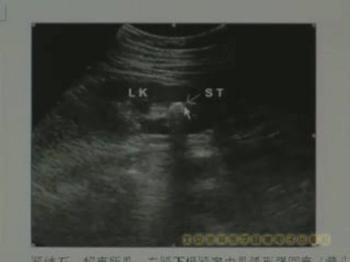

腎結石影像圖 |